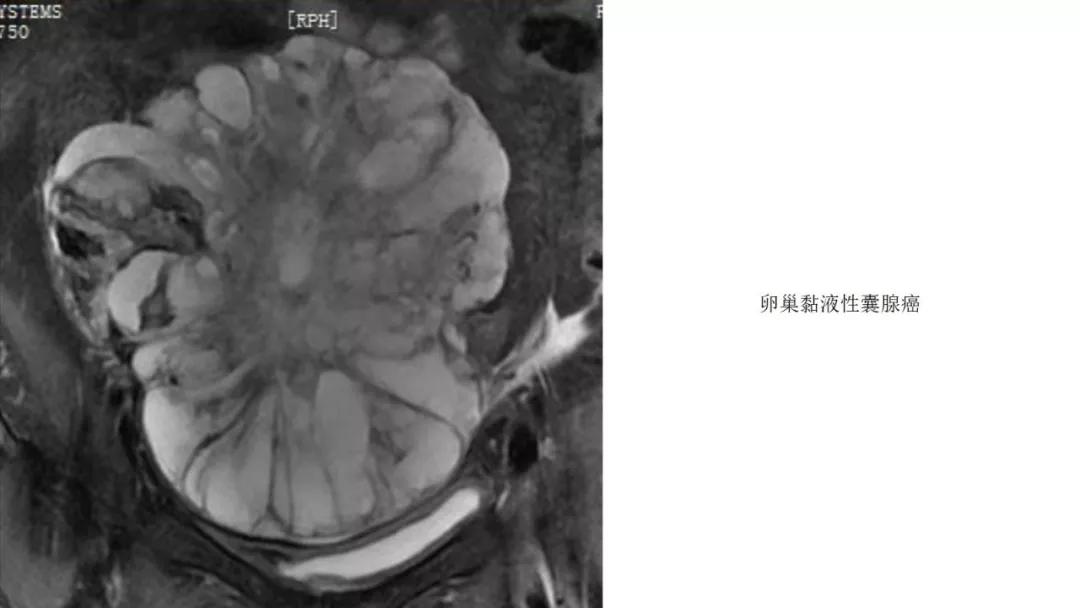

- 卵巢的黏液性肿瘤破裂,上皮和黏液会种植在腹膜引起胶冻样的腹膜假黏液瘤,这一点跟阑尾的黏液性肿瘤类似,都是腹膜假黏液瘤的病因。